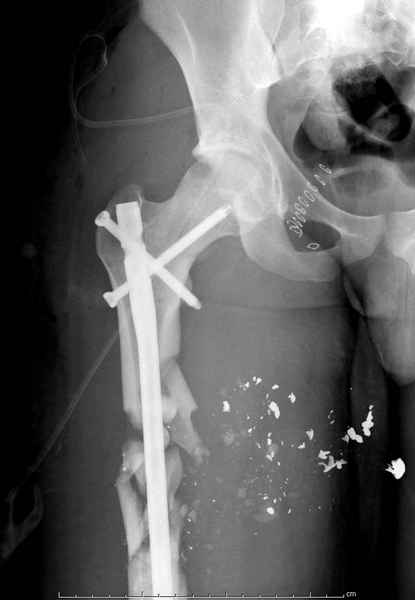

2 перелом бедра

Имя     : 1 GSW.jpg

Тип     : image/jpeg

Размер  : 16781 байтов

Описание: отсутствует

Url     : http://weborto.net:8080/pipermail/ortho/attachments/20090726/b21ae3ea/attachment-0015.jpg

----------- УМЕДХЭБС ЮБУФШ -----------

Вложение не в текстовом формате было извлечено…

Имя     : 2 GSW exfix.jpg

Размер  : 16470 байтов

Url     : http://weborto.net:8080/pipermail/ortho/attachments/20090726/b21ae3ea/attachment-0016.jpg

Имя     : 3 GSW final ap.jpg

Размер  : 25174 байтов

Url     : http://weborto.net:8080/pipermail/ortho/attachments/20090726/b21ae3ea/attachment-0017.jpg

Имя     : 4 GSW final lat.jpg

Размер  : 18190 байтов

Url     : http://weborto.net:8080/pipermail/ortho/attachments/20090726/b21ae3ea/attachment-0018.jpg